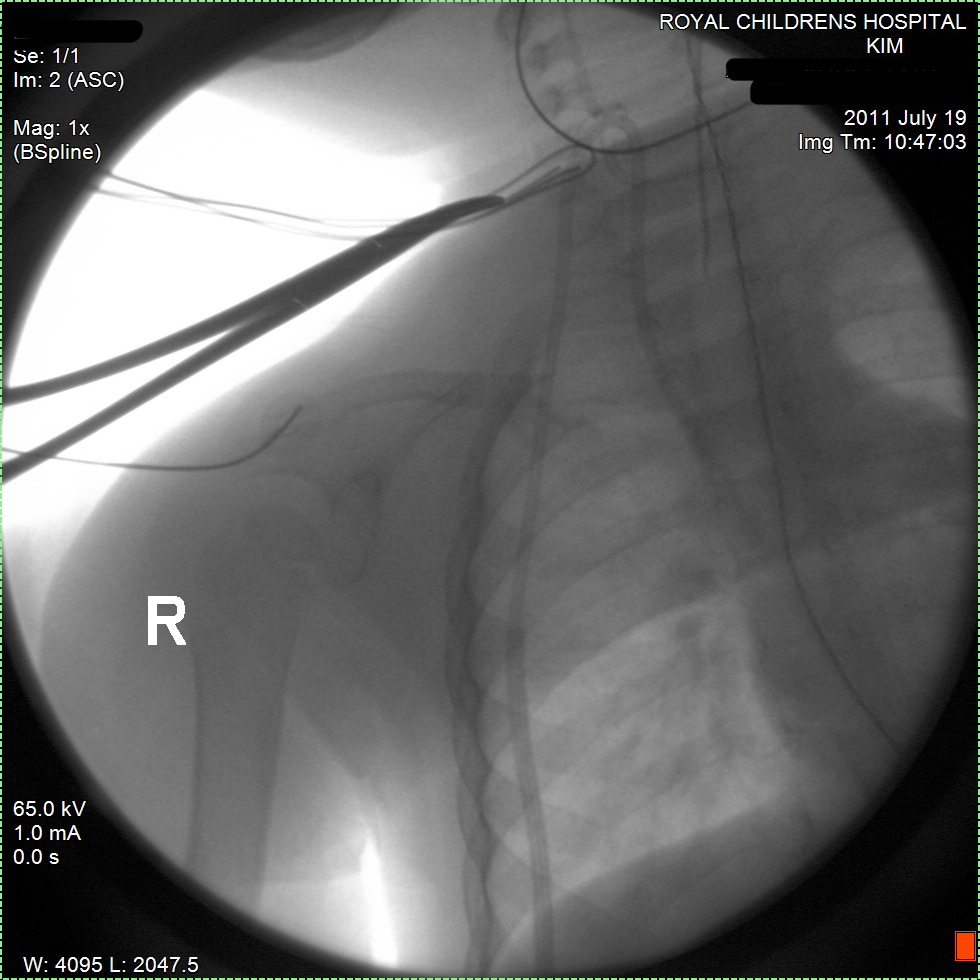

14:15-18:40 Laparoscopic Surgery removed the tumour and nodes near her artery. It was a clean removal and the tumour was taken out in one piece. Her kidney was pushed aside and partially encapsulated by the tumour but it seems it did not encroach into the kidney. The kidney could stay and a full recovery is expected. The surgeon inspected but did not find any nodes in pelvis area. The chemo has removed all the nodes. There were no complications.

30 September 2011, Friday